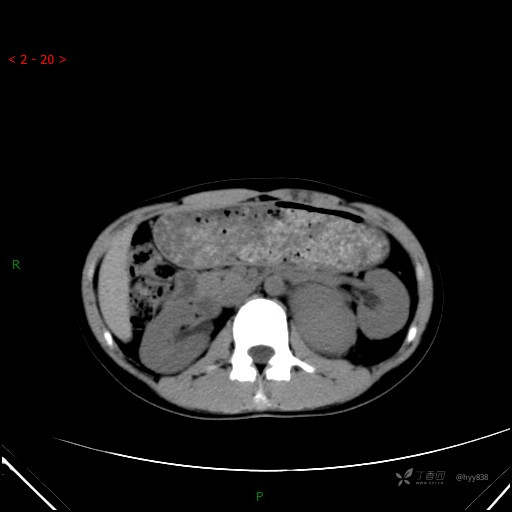

腹部CT平扫